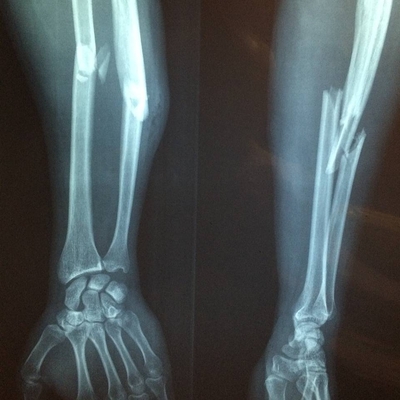

Click on an image below to view more info.